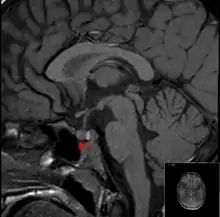

It is recommended that magnetic resonance imaging (MRI) scan of the pituitary gland is performed if the diagnosis is suspected; this has a sensitivity of over 90% for detecting pituitary apoplexy; it may demonstrate infarction (tissue damage due to a decreased blood supply) or hemorrhage.[1] Different MRI sequences can be used to establish when the apoplexy occurred, and the predominant form of damage (hemorrhage or infarction).[2] If MRI is not suitable (e.g. due to claustrophobia or the presence of metal-containing implants), a computed tomography (CT) scan may demonstrate abnormalities in the pituitary gland, although it is less reliable.[1] Many pituitary tumors (25%) are found to have areas of hemorrhagic infarction on MRI scans, but apoplexy is not said to exist unless it is accompanied by symptoms.[1][4]